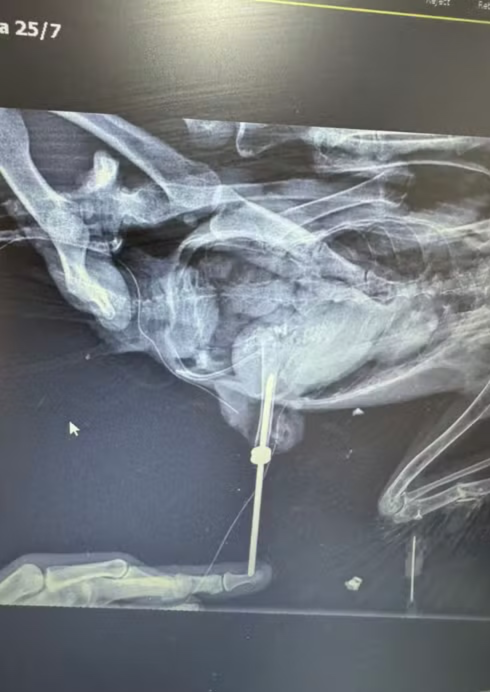

A avaliação clínica revelou déficit de propriocepção e atrofia muscular severa no membro, quadro confirmado por radiografia, que mostrou uma fratura antiga com reabsorção óssea. Diante do diagnóstico, a equipe decidiu pela amputação e implantação de uma prótese osseointegrada com pino medular, que permite a fixação direta ao osso.